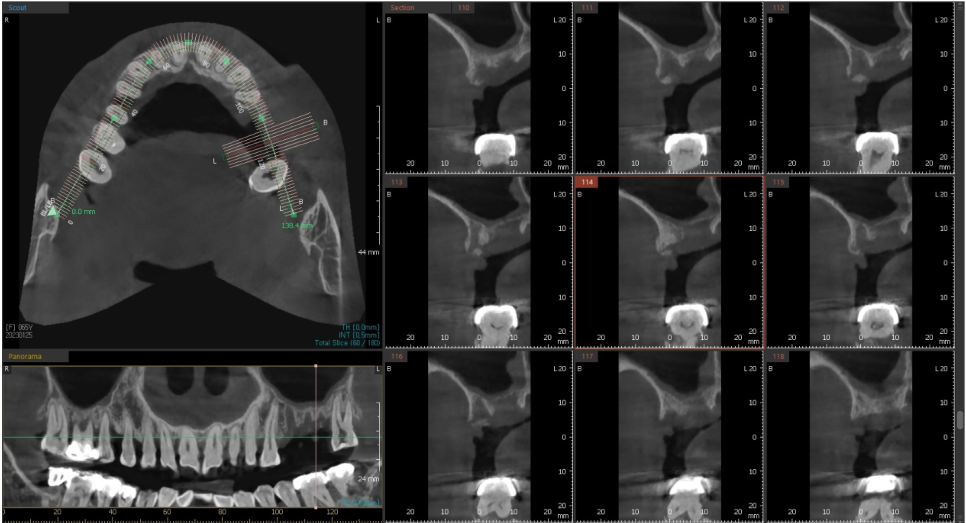

꼭 필요한 자리에만 뼈이식을 권유드리고 있습니다.

임플란트를 식립 하고

식립한 임플란트를 지지하기 위해서는

치조골이 필요한데

상악동 하방의 치조골 양이 부족한 경우

상악동 점막을 들어올리고

점막과 기존의 치조골 사이에

인공뼈를 이식함으로써

임플란트를 지지해 줄 수 있는

뼈를 만들어줘야 합니다.

이를 "상악동 거상술"이라고 합니다.

뿌리 끝 염증으로 인해 이미 뼈가 많이 녹아

인접한 치아들마저 흔들리는 상황이었기때문에

오래 방치할 수록 안좋은 상황입니다.

뿌리 끝 염증이 생겨 많이 흔들리는

첫번째 큰어금니와 그 앞의 작은 어금니를 발치 한 후

"상악동 거상술"과 함께 임플란트를 식립하기로 했습니다.